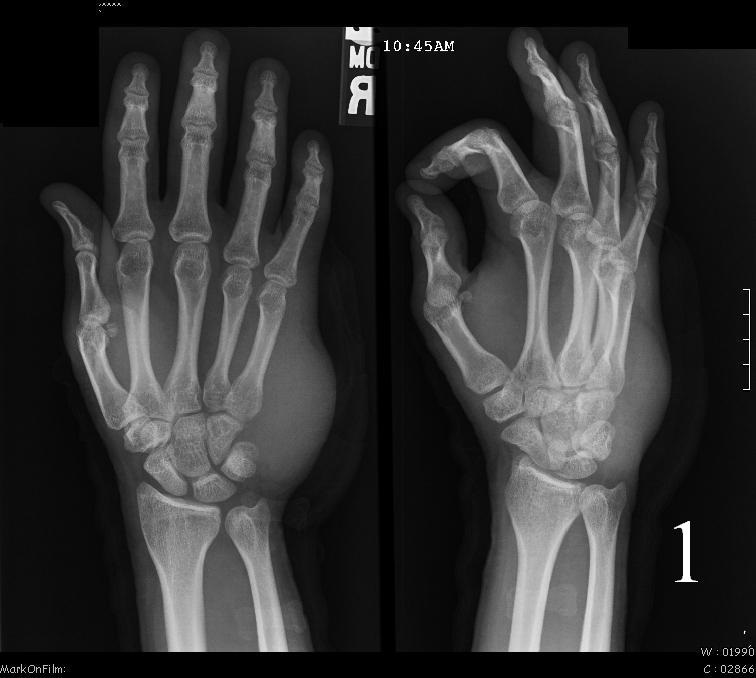

Plain x-ray

- No specific radiological features (Fig. 1)

- 24% of the cases invade adjacent bone

- No mineralization/calcification.